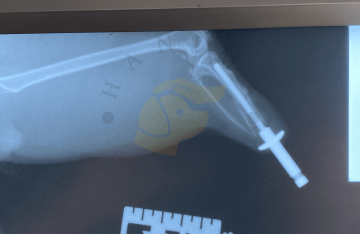

RTG vyšetření skeletu a kloubů